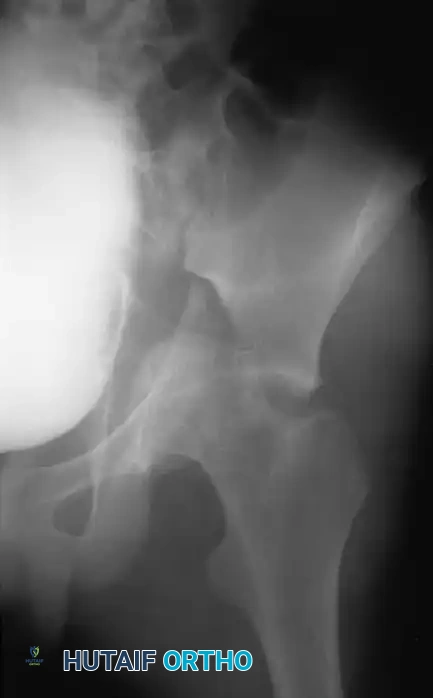

The evaluation begins with an Anteroposterior (AP) view of the pelvis, followed by the two Judet oblique views (Obturator Oblique and Iliac Oblique), taken at 45-degree angles.

Six fundamental radiographic landmarks must be identified on the AP radiograph to understand the fracture pattern:

1. Iliopectineal Line: Represents the anterior column.

2. Ilioischial Line: Represents the posterior column.

3. Radiographic Teardrop: Represents the medial wall of the acetabulum (anterior-inferior portion of the quadrilateral surface).

4. Roof of the Acetabulum: The superior weight-bearing dome.

5. Anterior Lip (Wall) of the Acetabulum.

6. Posterior Lip (Wall) of the Acetabulum.

Fractures traversing the anterior column disrupt the iliopectineal line, whereas posterior column fractures disrupt the ilioischial line.

Computed Tomography (CT):

CT scanning is mandatory. It defines the size of wall fragments, the presence of intra-articular loose bodies, marginal impaction, and the exact orientation of fracture lines. CT is particularly critical in identifying incarcerated fragments that block closed reduction of a dislocated hip.